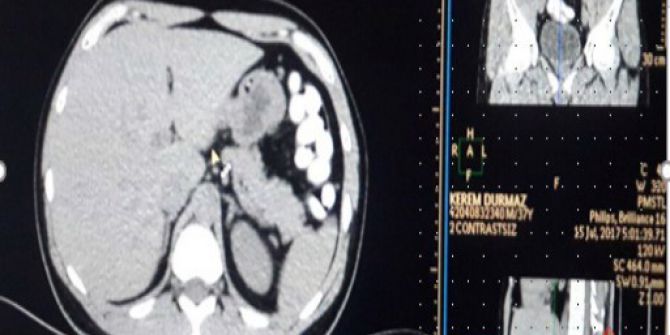

Faslı Uyuşturucu Kuryesinin Midesinden 78 Adet Kapsül Uyuşturucu Çıktı